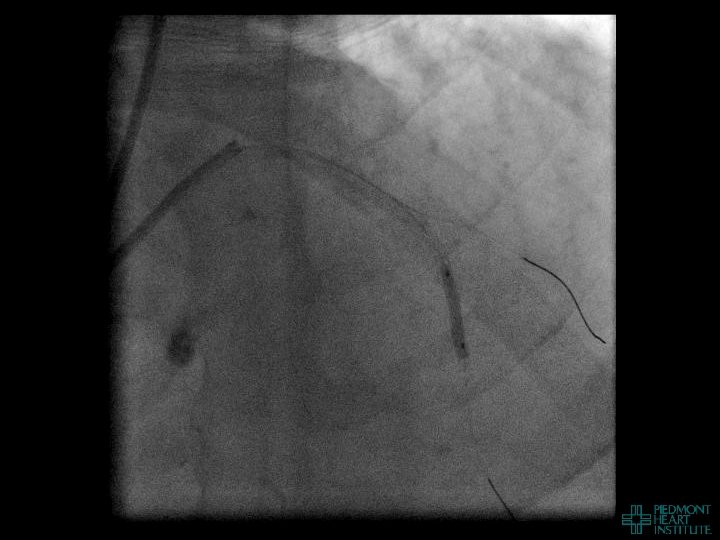

Coronary Perforation In CTO Revascularization Often does not occur at the occluded segment nor

Coronary Perforation In CTO Revascularization Often does not occur at the occluded segment nor is related to the guidewire… 12% CTO-related perforations due to balloon inflation, stent implantation, or atherectomy 1 Is not always manifest during the procedure… 45% events diagnosed after leaving the catheterization laboratory (mean time from PCI 4. 4 hrs)2 Is associated with substantial morbidity and mortality… Death (42%), emergency surgery (39%), MI (29%), transfusion (65%)2 1 Nakamura et al. AHA 2002, 2 Fejka, O’Neill et al. AJC 2002

Coronary Perforation Methods of Patient Management • Dual Catheter (‘Ping Pong’) Technique • Prolonged

Coronary Perforation Methods of Patient Management • Dual Catheter (‘Ping Pong’) Technique • Prolonged balloon inflation and covered stents • Reversal of anticoagulation — Know contradictions to protamine sulfate for UFH; Avoid bivalirudin, LMWH — Reserve GP 2 b 3 a inhibition until successful crossing and wire change-out Embolization • — Coil, gelfoam, methacrylate, autologous blood/fat • Microcatheter Occlusion • Confirmation of successful management — Contralateral injection — Right heart catheterization — Echocardiogram — Contrast echocardiography